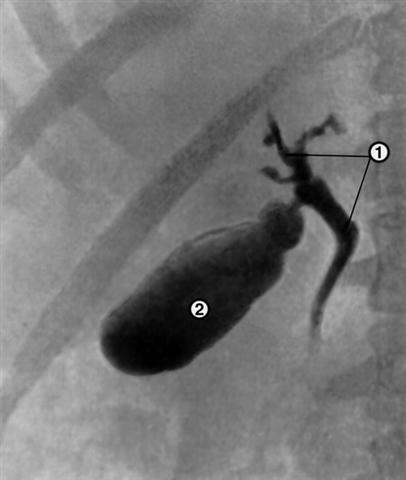

Рис. 1. Холеграмма в норме: 1 — тени крупных желчных протоков; 2 — тень желчного пузыря.